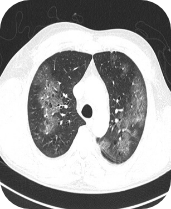

Chest computerised tomography (CT):

Bilateral ground glass opacities and a small

consolidation in the left lower lung lobe

Images supplied with permission of treating clinician.